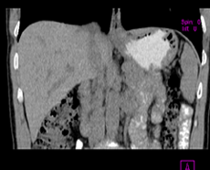

患者,男,57,常年不吃午饭,近一个月来腹部隐痛,无明显黄疸,明天进行增强扫描,图象另上传,麻烦各位帮忙一起看看讨论讨论

肝外胆管扩张,胰头增大,肠系膜上静脉似有包埋征象。

考虑:胰头占位性病变,建议增强进一步检查。

肝外胆管扩张,胰头增大,占位性病变可能性大.

肝外胆管稍扩张,胰腺钩突略增大,但外形尚可,境界清楚。(常年不吃午饭)提示胰腺炎可能大,肿瘤第二步考虑。

支持考胰头占位性病变,感觉十二指肠壁不规则增厚,不排除十二指肠降部占位可炎症

胰头增大,考虑胰头占位性病变。

胰头增大,胆总管增宽,考虑胰头癌可能性大,明天看增强片有助诊断.